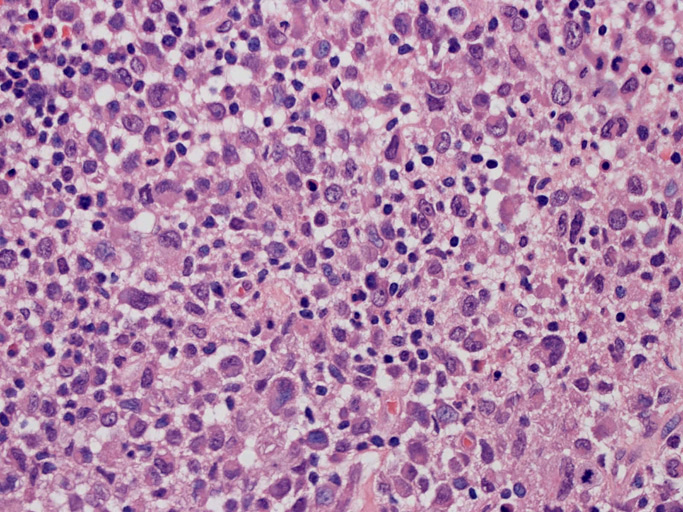

大型細胞の増殖よりなる腫瘍。縦溝,しわ,切れ込みのある核をもった大型細胞も出現する。クロマチンは顆粒状で核小体も明瞭である。核分裂は >50/10hpfと多い。eosinophilsは少ない。壊死が多発することがある。未分化ないし低分化な細胞像, 組織所見のため鑑別診断は多岐にわたり、的確な免疫染色を行う必要がある。

皮膚に異型細胞の浸潤がみられる。異型細胞は表皮内に浸潤するほか、表皮真皮境界部, 真皮, 皮下脂肪組織にもびまん, 結節様の浸潤所見を示す。血管周囲に浸潤、集蔟する所見も多く見られる。 増殖浸潤細胞の核には類円形や腎臓形, またはへこみ, 切れ込み, 溝などを有する多型な核が認められる。クロマチンは粗でvesicularな核が多い。核小体の明らかな核もある。好エオジン性の核内封入体様構造も少数に見られた。mitosisは容易に認められる。hyperchromaticな多型核, bizzarreな細胞が高頻度に認められ異型度は高いと考えられる。細胞質は境界不明瞭, 淡明または泡沫様の 好エオジン性胞体である。

免疫染色 浸潤細胞はCD1a+, S100+, Langerin+, HLA-DR+, CD4+, CD45+, CD68+. MIB-1 index:24.4%